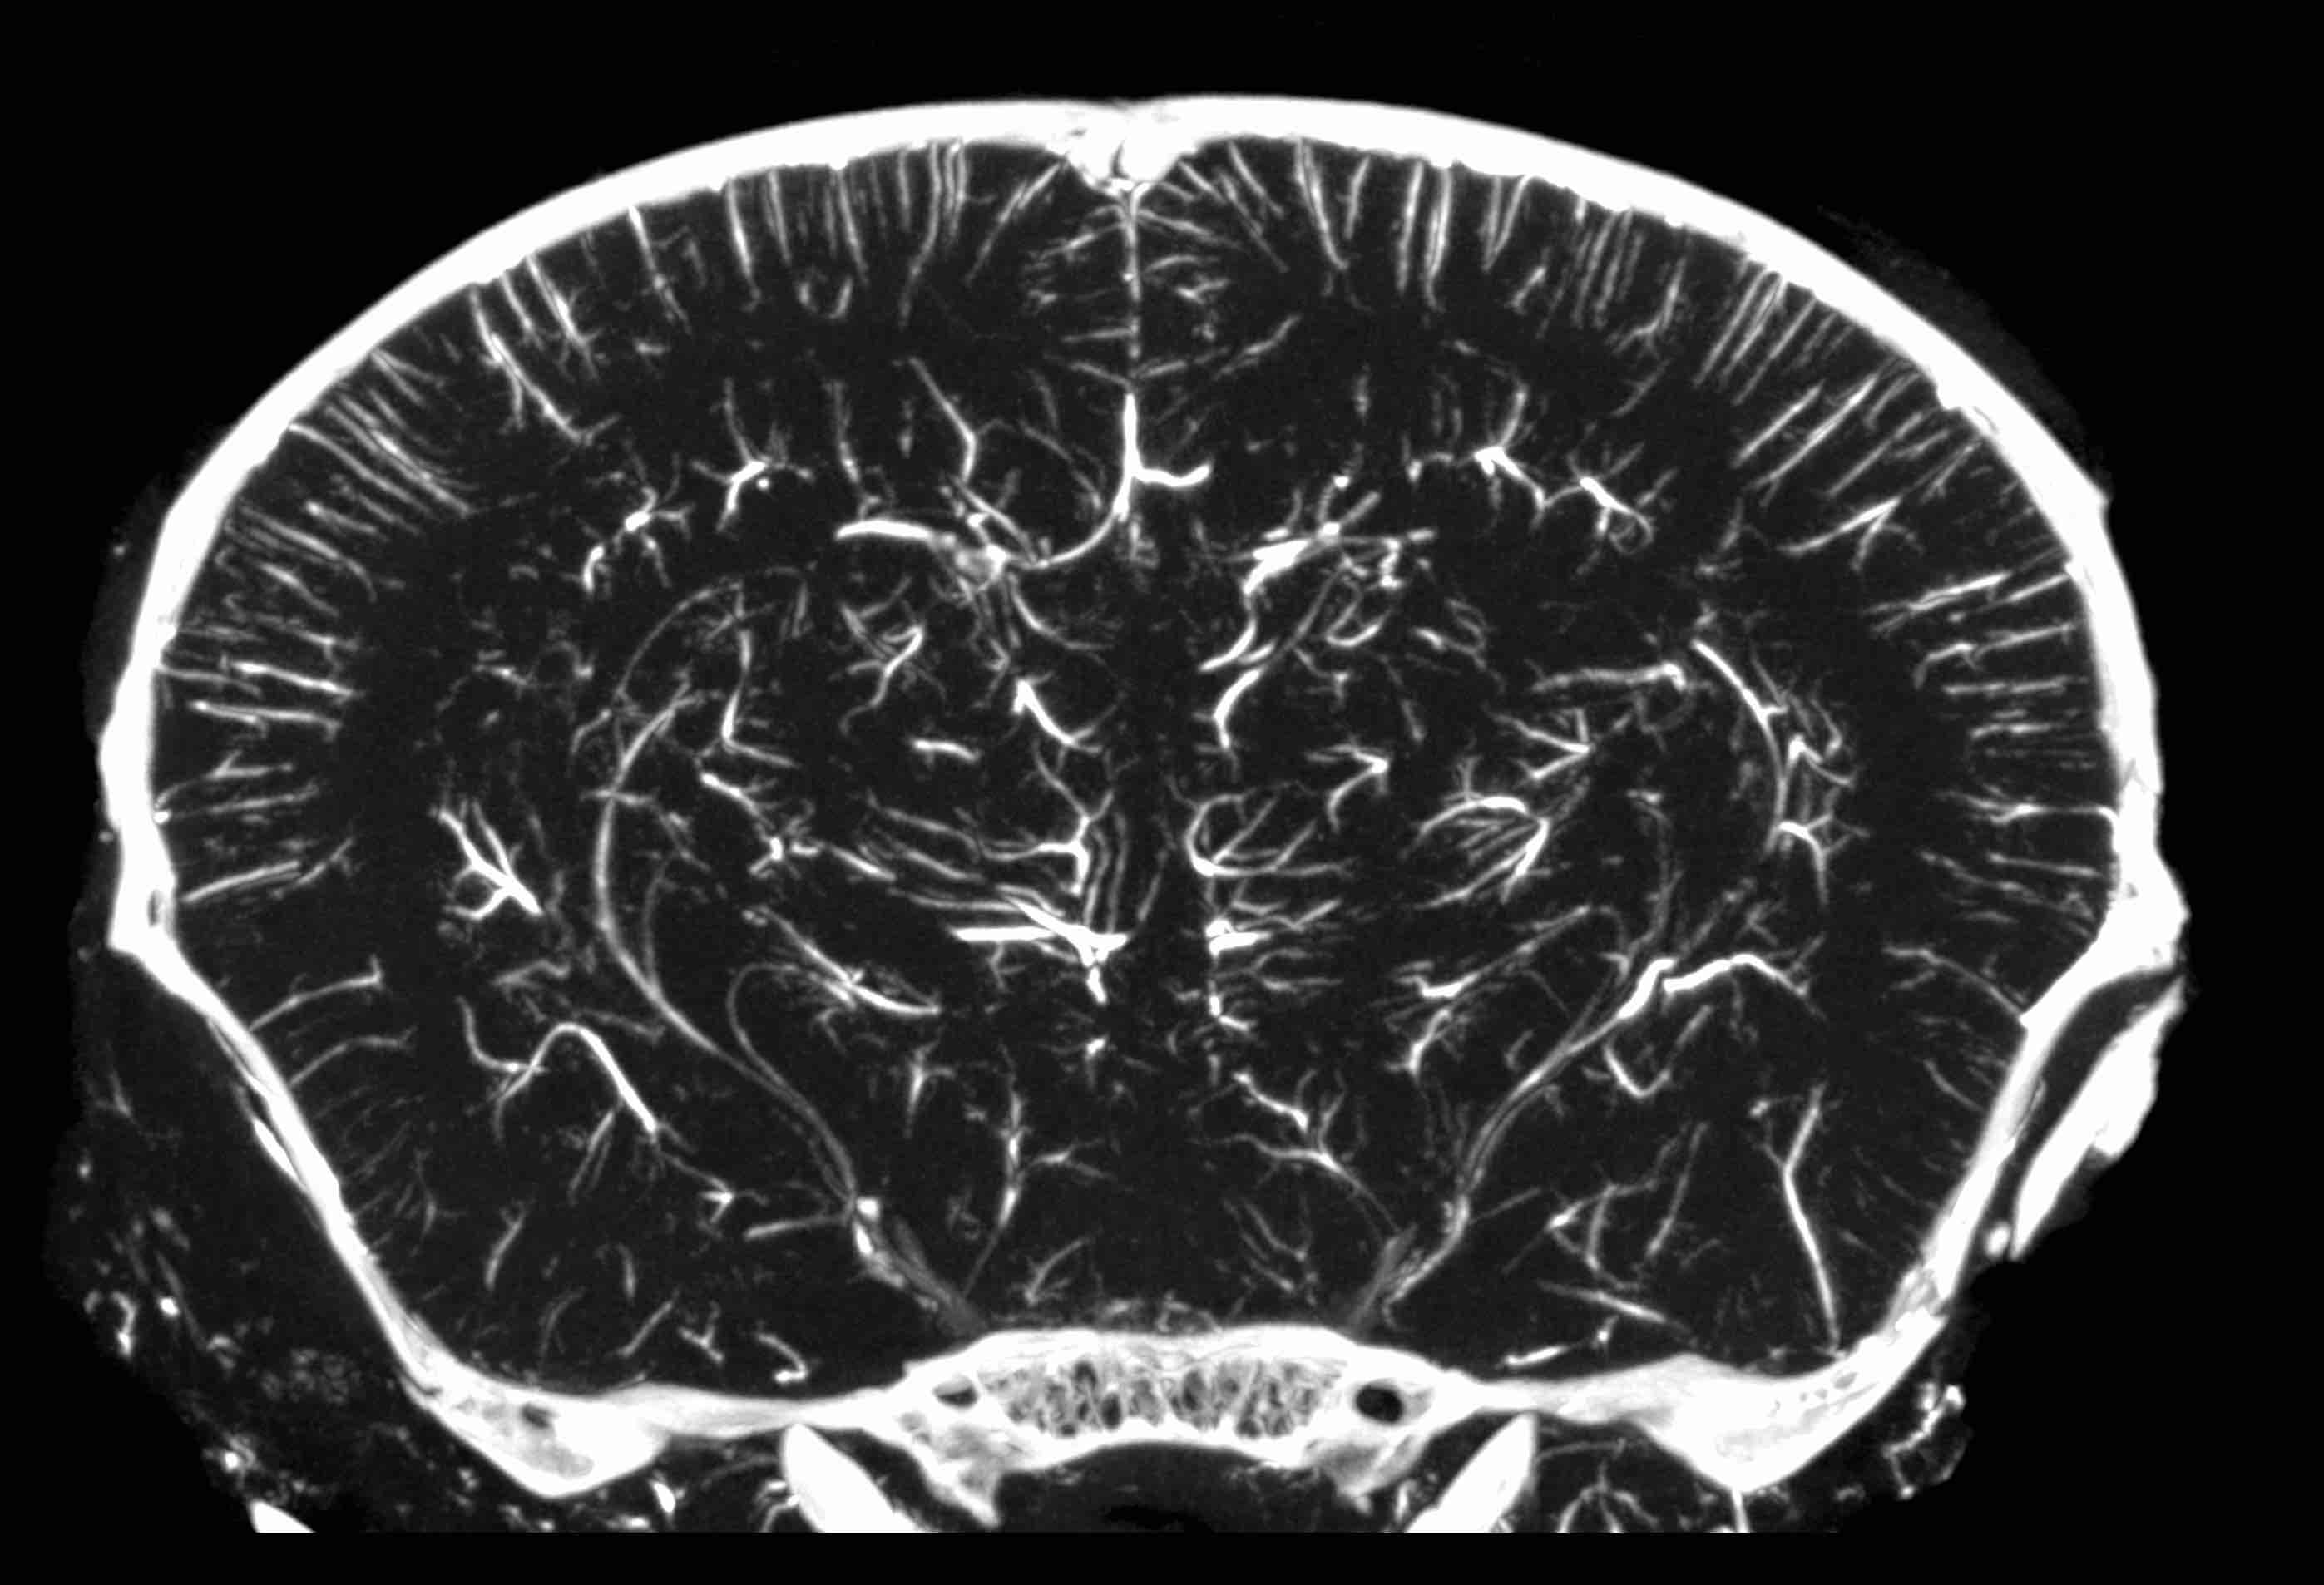

Ex vivo imaging of cerebral vasculature with perfused contrast agent (Photo: Marrelli Lab)